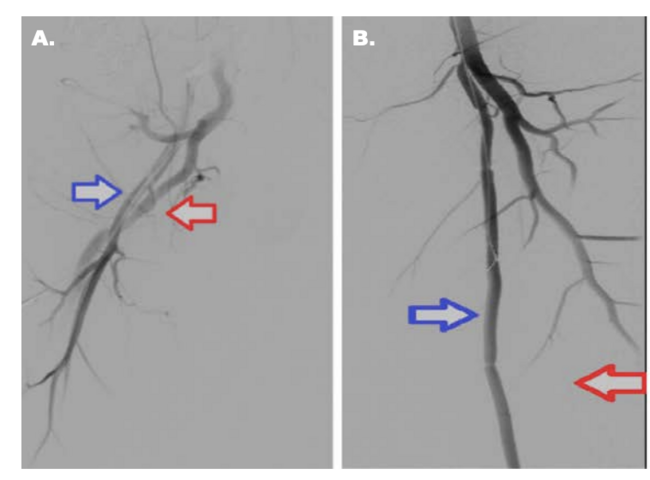

Without further imaging diagnostics, conventional angiography was performed, revealing bilateral persistent sciatic artery type 2a7,8, with ostial occlusion of the left PSA and distal filling from a collateral arising from an otherwise rudimentary SFA. Additionally, acute thrombosis of a high take-off anterior tibial artery (ATA) and a recanalized thrombosis of the proximal segment of the popliteal artery (PA) with distal collateral filling were observed (Figure 1). Through right femoral access, a 45 cm, 6 French crossover guiding sheath (Flexor Ansel Guiding Sheath, Cook Medical) was placed in the left PSA over a .035-inch Storq Soft guidewire (Cordis, A Cardinal Health Company). Additionally, a TrailBlazer .035-inch support catheter (Medtronic) and a hydrophilic Half Stiff Angled J .035-inch guidewire (Terumo) were used to get through the occlusion of the PSA – first retrograde, using the collateral from the SFA, and then antegrade. Balloon angioplasty was performed using a 5.0 mm × 300 mm over .035-inch Admiral Xtreme (Medtronic) balloon catheter, followed by implantation of 3 overlapping stents: EverFlex 6.0 mm × 150 mm, EverFlex 7.0 mm × 150 mm (Medtronic), and a Complete SE 7.0 mm × 20 mm (Complete) due to remaining significant stenoses. To cross the thrombosis of the ATA and the recanalized thrombosis of the PA, a .014-inch Asahi Sion ( Asahi Intecc) guidewire was used and balloon angioplasty was performed with a 2.5 mm × 100 mm over .014-inch Pacific Xtreme (Medtronic Medical) balloon catheter (Figure 2). An excellent result was noted for the treated lesions. The patient's postprocedure period was unremarkable, and he was discharged the following day with an ABI of 0.81 in the left leg. Double antiplatelet therapy in standard doses with acetylsalicylic acid and clopidogrel was initiated. On day 15 of the first and third month of the follow-up period, marked clinical improvement was noted, with the patient being able to walk for more than a kilometer with no claudication, a Doppler ultrasonography examination revealed patent stents.